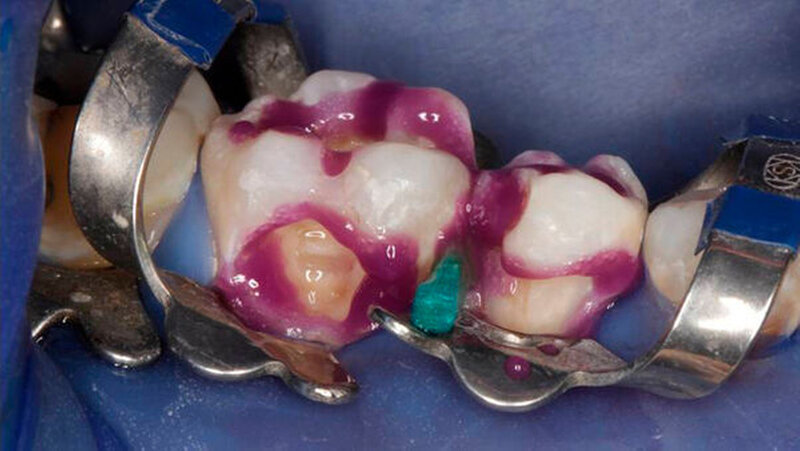

Die Behandlung umfasste zwei Termine (erster: Zahn 46 und 45, zweiter: Zahn 43 und 44). Zur Entfernung der alten Füllungen dienten ein runder und ein zylindrischer Diamantbohrer sowie langsam laufende Hartmetallbohrer und zur Feinbearbeitung der Kavitäten ein Ultraschallinstrument. Nach selektiver Schmelzätzung applizierte man das Adhäsiv XP BOND®. Das Dentin wurde durch SDR ® ersetzt. Dann wurden mit ceram.x one® d3 und e2 jeweils der Rest der Kavität und die Höcker restauriert. Finiert und poliert wurde mit dem Soflex Poliersystem.

Die Restaurationen erfolgten minimal-invasiv. Durch Wiederherstellung der natürlichen Morphologie wurde für eine stabile Okklusion gesorgt. Auch bei der Kontrolle nach 9 Monaten machten die Füllungen morphologisch und farblich einen guten Eindruck. Ästhetik und Funktion gingen Hand in Hand.